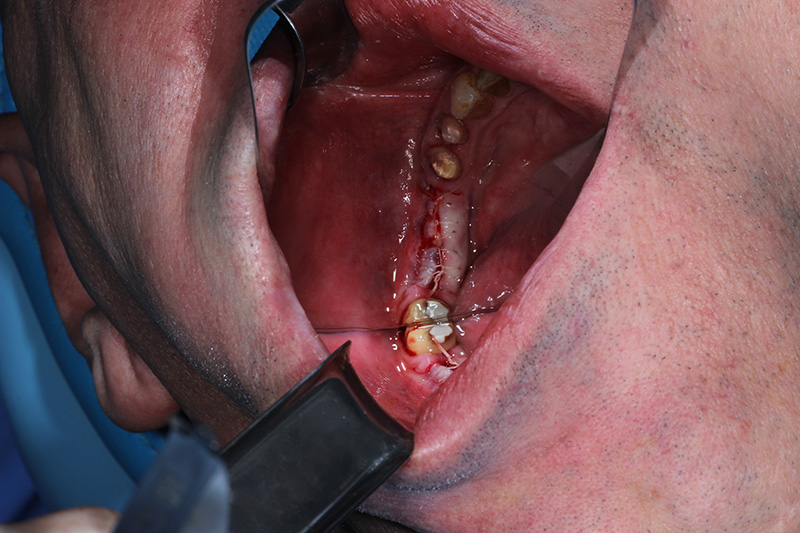

26-ого октября в учебном центре Стом-Лайн был проведен мастер-класс на тему «Закрытый и открытый синус-лифтинг при имплантации, с использованием имплантатов Thommen Medical». Мастер-класс провел главный врач-стоматолог клиники «Нюанс» в Москве Мхитар Казарян.

Мастер-класс начался с представления швейцарских имплантатов Thommen Medical, официальным предтсвителем которых является клиника Стом-Лайн. Далее были проведены обсуждения предстоящей операции и исследования компьютерной томографии, после чего участники смогли присутствовать на операции или следить за ней из учебного центра.

Во время операции доктор Казарян представил на практике особенности и преимущества имплантатов Thommen Medical.